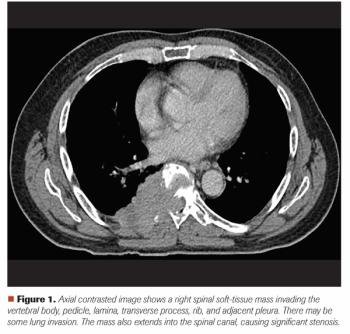

ABSTRACT: Breast metastasis from extramammary malignancy is rare, with a reported incidence rate of 0.4% to 1.3% in the published literature. The primary malignancies that most commonly metastasize to the breast are leukemia, lymphoma, and malignant melanoma. Here, we report a very rare case of metastatic EGFR-mutated non–small cell lung cancer (NSCLC) in the breast detected by screening mammography. The patient had initially been diagnosed with a clinical stage IIIA NSCLC and had been treated with neoadjuvant chemoradiation followed by curative-intent surgery. Several interesting aspects of the case, along with a discussion of evolving adjuvant and frontline metastatic management options in EGFR-mutated NSCLC, will be presented.